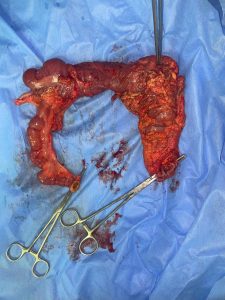

وأوضح الدكتور أحمد كمال المدير التنفيذى للمستشفيات الجامعية أته تم إجراء العملية الجراحية لاستئصال الورم بنجاح، مع الحفاظ على الوظائف الحيوية للأمعاء، مشيرًا الى أن الحالة العامة للمريضة مستقرة، وتخضع الآن للمتابعة الدقيقة فى قسم الرعاية ما بعد الجراحة.

وذكر الدكتور علاء السيوطي رئيس قسم الجراحة العامة أنه تم تشكيل الفريق الطبى بقيادة الدكتور مينا ظريف أستاذ الجراحة العامة وجراحة الأورام، وضم كلًّا من، الدكتور مايكل أشرف مدرس مساعد، الدكتور عادل أشرف، الدكتور عبد الله أبو المجد، الدكتور كيرلس محارب أطباء مقيمين، وذلك بالتعاون مع فريق التمريض والتخدير.